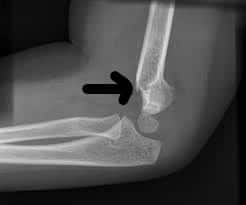

Complications of the fracture shown in the picture below are all except ?

The fracture shown in the picture above represents supracondylar fracture of humerus.

Complication is non union.